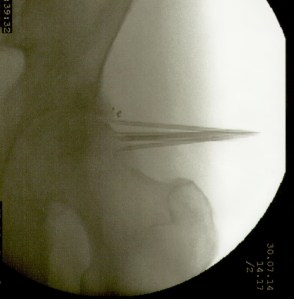

Más abajo se observarán unas imágenes de casos de implantes de oro en cadera

La artroplastia total de cadera para los casos de coxartrosis severa es el tratamiento de elección de la gran mayoría de cirujanos ortopédicos. Sin embargo cuando el paciente es menor de 50 años suele diferirse la intervención debido al tiempo de sobrevida del material protésico. También lo es en pacientes con deterioro del estado general debido a la avanzada edad o a enfermedades concomitantes (cardiópatas, por ej.) En estos casos la colocación de microimplantes de oro periarticulares alrededor del cuadrante súpero externo de la articulación es, habida cuenta del resultado sintomático y funcional, el tratamiento más indicado. La fácil colocación mediante control radioscópico y la rapidez de la recuperación (inmediata) hacen que este procedimiento sea seguro y muy útil para la remisión del dolor y la rigidez. No necesita ingreso ya que es una cirugía ambulatoria, se efectúa con anestesia local, y el paciente sólo requiere reposo relativo en el día de la intervención. Los resultados mediatos son excelentes. La mejoría clínica aumenta con los meses debido a la difusión de las nanopartículas de oro, por lo que contrariamente a los tratamientos convencionales que disminuyen su efecto con el tiempo, los microimplantes de oro lo mejoran. En cuanto esta técnica se popularice se reducirá significativamente el número de artroplastias.